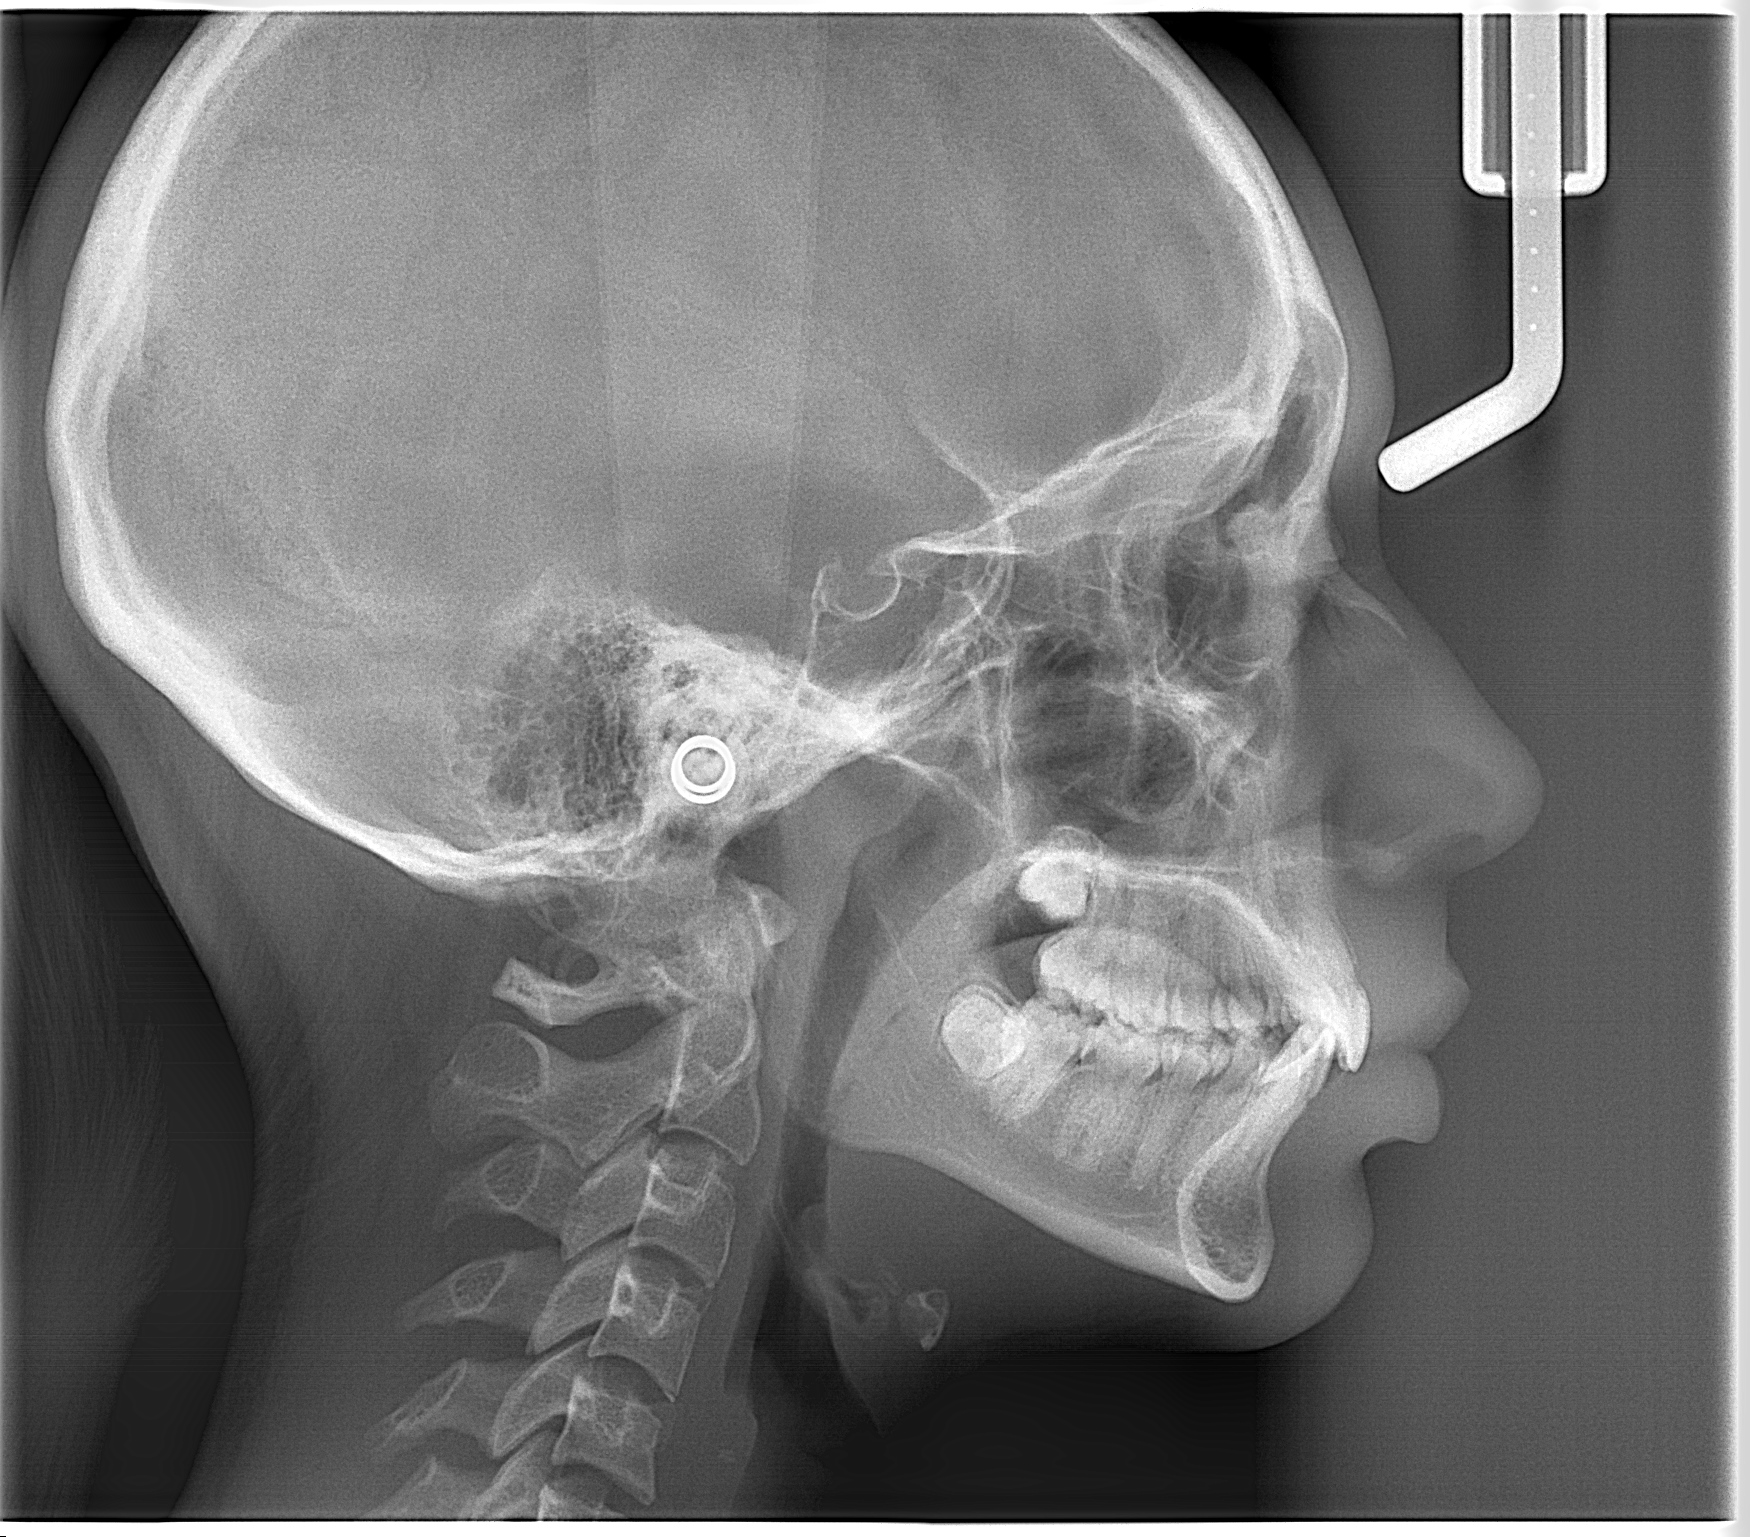

- Radiografía cefálica lateral: Radiografía extraoral que permite evaluar permeabilidad de vía área, ver el tamaño y posición de los maxilares, permite identificar la relación intermaxilar, entre otros.

Esta radiografía ayuda a evaluar la permeabilidad de vías aéreas, el tamaño y posición de los maxilares, y la relación intermaxilar.